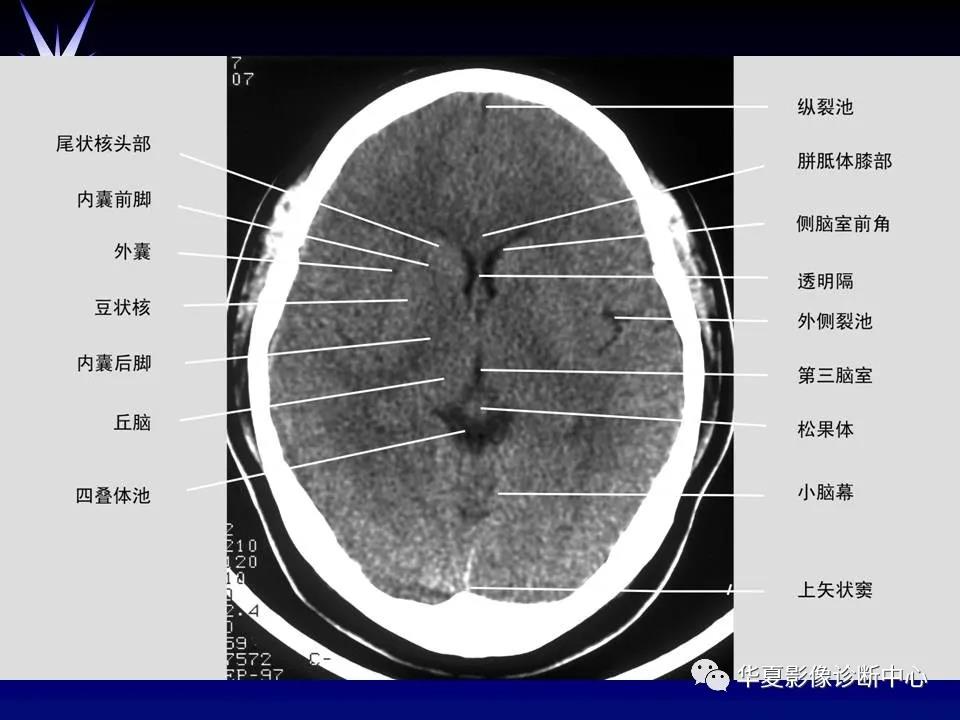

来源:华夏影像诊断中心